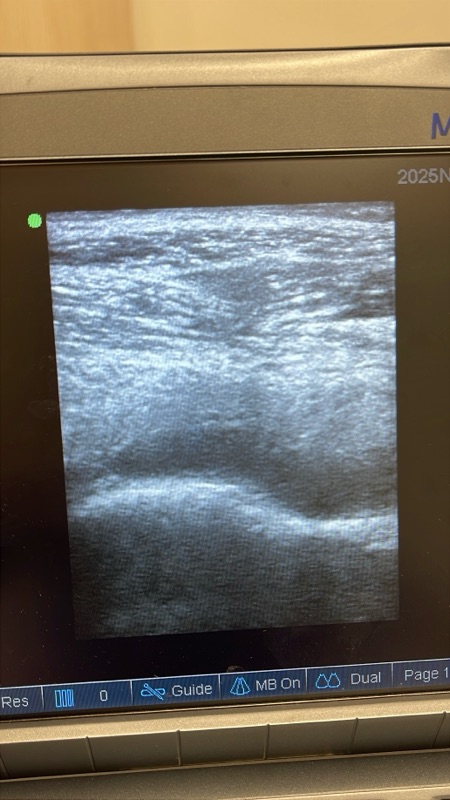

หลังตรวจด้วยอัลตราซาวด์พบว่า มีน้ำในข้อสะโพกจำนวนมาก (significant hip joint effusion) แม้เอกซเรย์จะ “ปกติ” ไม่มีรอยกระดูกหักก็ตาม

✔ 2) อัลตราซาวด์สะโพก

เป็นการตรวจที่ปลอดภัย เห็นน้ำในข้อได้ชัด และช่วยนำทางในการเจาะข้อ